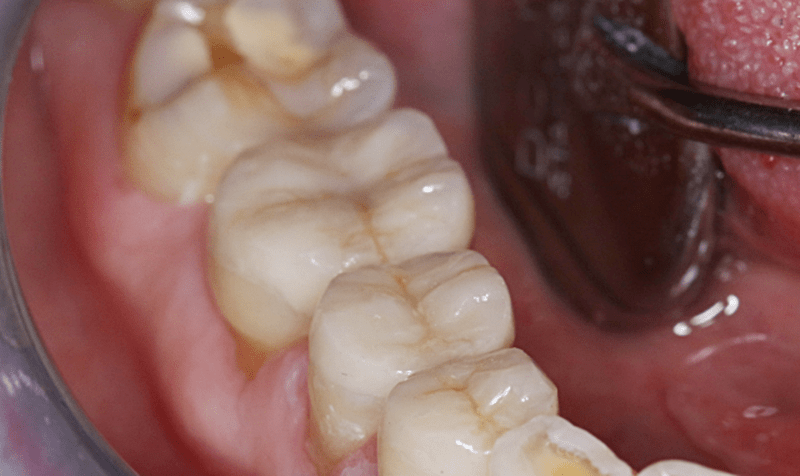

A végleges betétek általában egy hét alatt készülnek el, így a páciensnek vissza kell fáradni a rendelőbe. Ilyenkor a szakorvos ellenőrzi, majd beragasztja a kész betéteket. Íme, a szép és tartós végeredmény!

Amalgámtömések cseréje betétekre utána